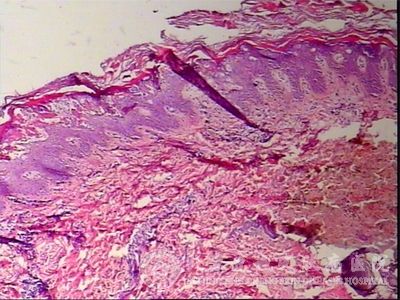

北京京城皮肤医院指出,表皮松解性角化过度鱼鳞病的组织病理表现为:表皮角化过度,颗粒*层增厚,棘层上部*有网状空泡化,有时桥粒仅与一侧棘*相连表皮*有棘突松解,表皮内可见有水疤或大疤, 浅层有慢性炎症浸润。